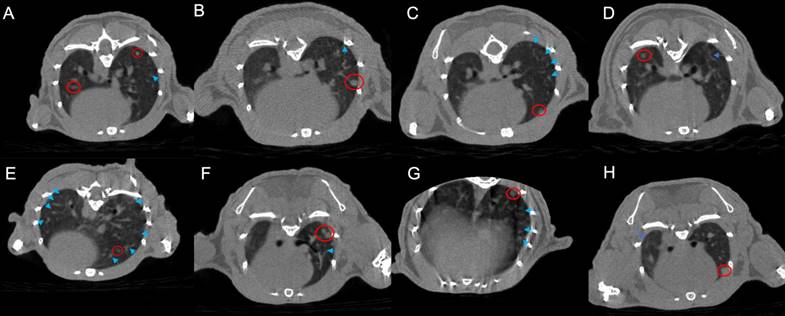

Observation of pulmonary inflammatory response by micro-CT scanning

Based on CT images, the radiotherapy group exhibits a greater manifestation of pulmonary inflammation compared to the PD-1 group. This observation is evident in both the comparison between the monotherapy radiotherapy group and the PD-1 group, as well as in the comparison between the combination therapy of radiotherapy and antibiotics and the combination therapy of PD-1 and antibiotics. Furthermore, our primary focus, the group that received PD-1 combined with radiotherapy, indeed demonstrates the highest degree of pulmonary inflammation among the eight groups. Interestingly, the triple combination group of PD-1/radiotherapy/antibiotics does not exhibit a higher level of pulmonary inflammation than the radiotherapy monotherapy group (Figure 1).

Figure 1

Micro-CT images of lung metastases in tumor-bearing mice across the eight experimental groups. A. control; B. PD-1; C. Radiotherapy; D. antibiotic; E. PD-1 + Radiotherapy; F. PD-1 + antibiotic; G. Radiotherapy + antibiotic; H. PD-1 + Radiotherapy + antibiotic. The bright blue arrows point to areas of inflammation in the lungs, and the bright red circle shows the tumor.